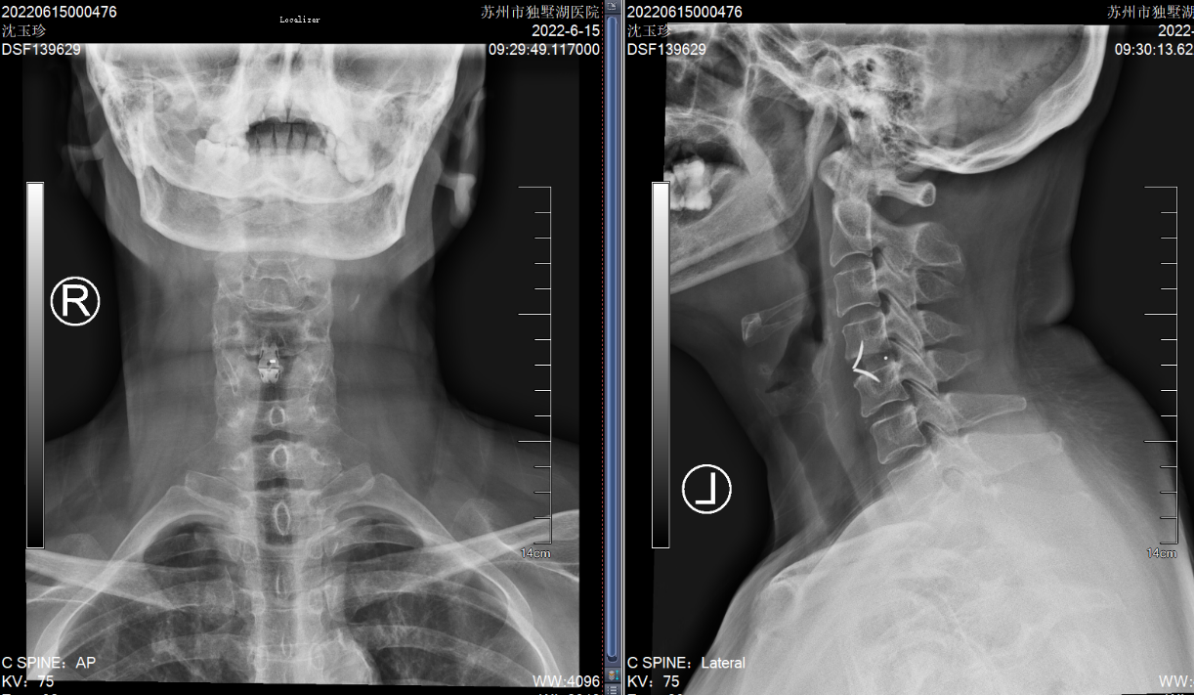

沈阿姨今年58岁,原本正是准备享受生活的年纪,但在今年5月,困扰了她长达4年的颈肩痛明显加重了。短短一周时间,沈阿姨的右上肢就出现了麻木感,吃药、理疗完全无法缓解,症状发展很快,于是立刻来我院骨科就诊。颈椎CT上可以清晰看到,她C4-5的椎间盘明显向右后方突出,椎间隙后缘骨赘增生,导致神经根受压。

(颈椎CT提示患者C5-6的椎间盘突出棒骨性狭窄)

意识到问题的严重,沈阿姨要求尽快手术治疗,于是在入院后的第二天,姜主任为她进行了颈椎前路椎间盘切除+椎间融合术(ACDF术)。手术起到了“精准减压”的效果,通过颈部一个3cm左右的横行小切口,准确到达病灶所在位置,解除神经根压迫,术后她颈肩痛的症状立刻得到了缓解,可谓“术到病除”。

(颈椎CT提示患者C4-5的椎间盘突出(右后方),椎间隙后缘骨赘增生)